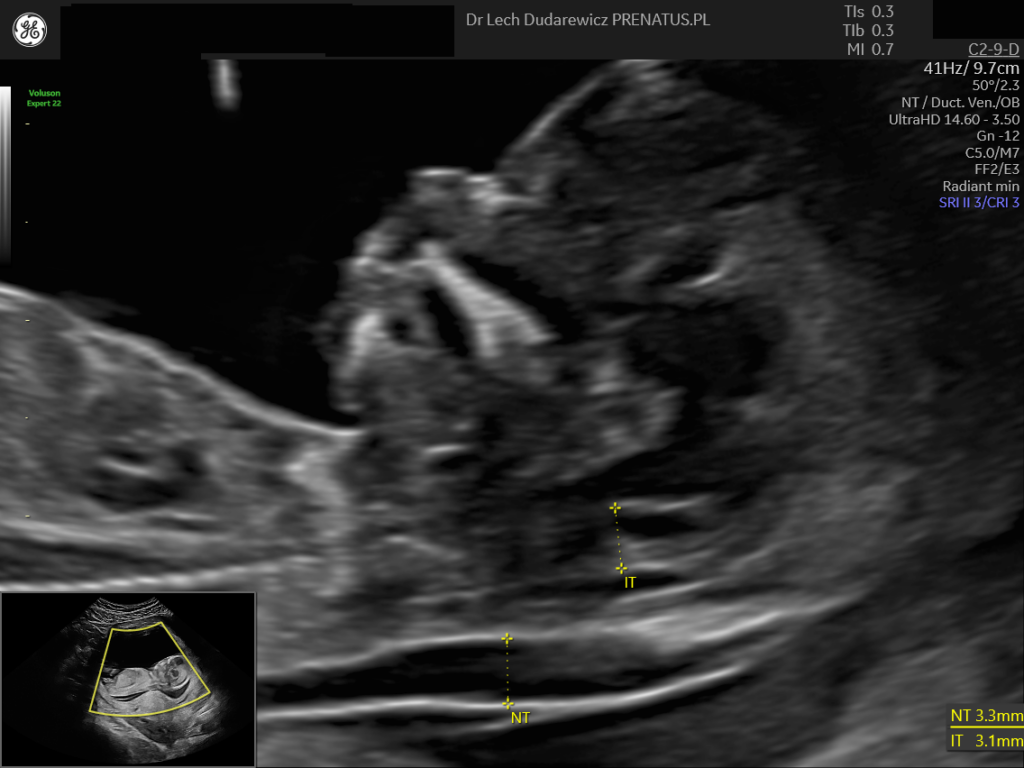

NT – Nieprawidłowy obraz przezierności karkowej płodu grubości 3,3 mm w 13 tygNT – Nieprawidłowy obraz przezierności karkowej płodu grubości 3,3 mm w 13 tyg

Dla lekarza wykonującego badanie skriningowe zwiększona NT w ciąży działa jak „czerwona lampka”.

Oznacza to komunikat:

„Coś odbiega od normy statystycznej – konieczna jest konsultacja u eksperta diagnostyki prenatalnej”.